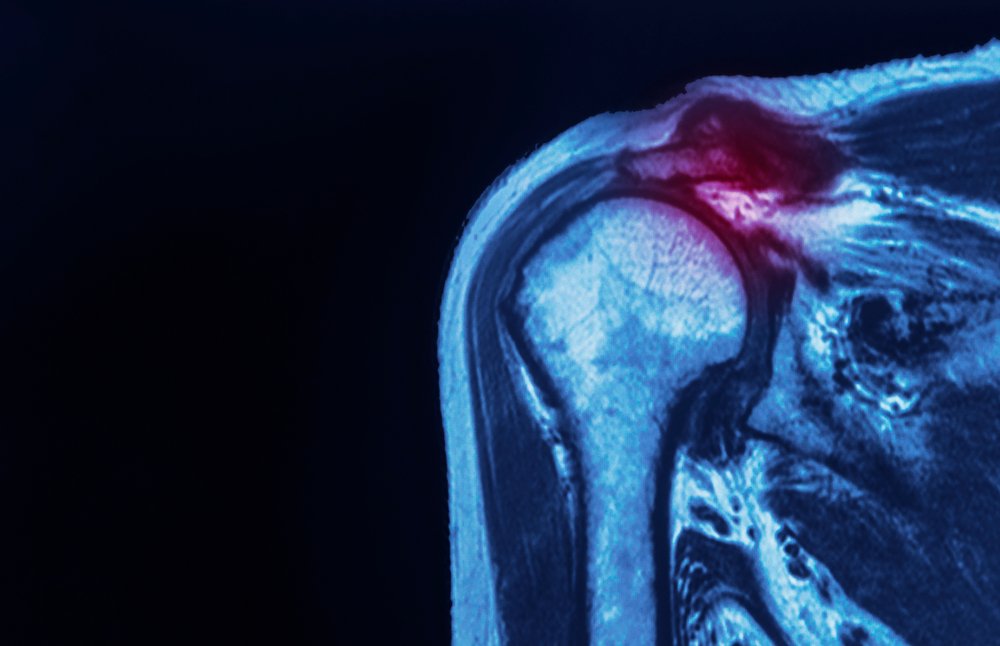

Роль визуализации в диагностике разрыва вращательной манжеты плеча

Визуализирующие исследования играют ключевую роль в диагностике повреждений вращательной манжеты плеча.

Рентгенография может выявить костные шпоры или структурные проблемы головки плечевой кости и кости плеча, а магнитно-резонансная томография (МРТ) и ультразвук позволяют получить детальное изображение мышц вращающей манжеты плеча, сухожилий и лопатки.

Эти инструменты помогают дифференцировать частичные разрывы, дегенеративные разрывы и полнослойные разрывы, обеспечивая точный диагноз и позволяя составить индивидуальный план восстановления вращательной манжеты.